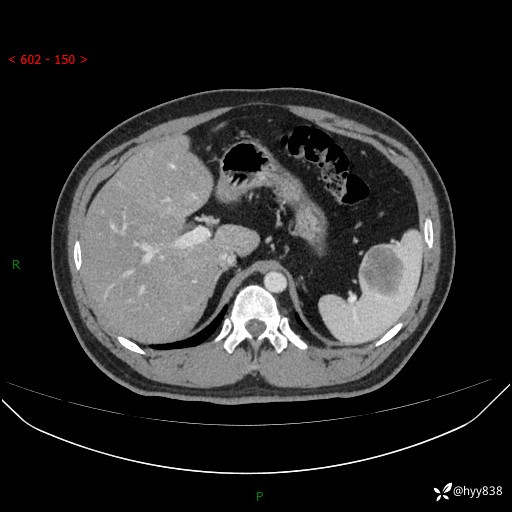

【患者信息】:31岁/男

【主诉】:超声发现脾脏肿物,为进一步诊治来我院,门诊以“脾脏占位”收入院

【检查】:上腹部CT平扫+增强